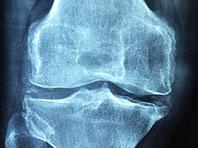

Китайские ученые выявили новую терапевтическую мишень, воздействие на которую может омолодить стареющие клетки. Это потенциальное спасение от остеоартрита, пишет Xinhua. Данный недуг характеризуется дегенерацией суставной хрящевой ткани.

Старение и истощение мезенхимальных стволовых клеток считаются основными причинами развития остеоартрита. Следовательно, выявление молекулярных механизмов старения мезенхимальных стволовых клеток даст ключ к эффективному лечению остеоартрита, говорят эксперты.

Сотрудники Института биофизики Китайской академии наук, Пекинского университета и Института зоологии обратили внимание на белок CBX4. Он защищает мезенхимальные стволовые клетки от клеточного старения, тем самым, контролируя развитие остеоартрита.

Эксперименты на мышах показывают, что излишняя экспрессия CBX4 тормозит клеточное старение, купирует воспаление и стимулирует регенерацию хряща. По словам специалистов, генная терапия, предполагающая воздействие на CBX4, может реально изменить состояние пациентов с остеоартритом.